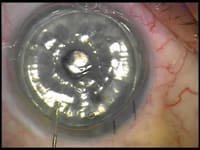

Occasionally, this unfolding process can be aided with a Sinskey hook or even an I&A. The unfolding requires a deep anterior chamber, and I avoid the endothelium. The tissue is then centered by using finger ballottement at the limbus easily pushing the donor tissue in place. The anterior chamber needs to be only partially deep for this movement. Lastly, a large air bubble is injected under the donor tissue, filling close to 100% of the anterior chamber (Figure 2).

Figure 2. An air bubble under the donor tissue

is created filling the anterior chamber of the recipient's eye. |